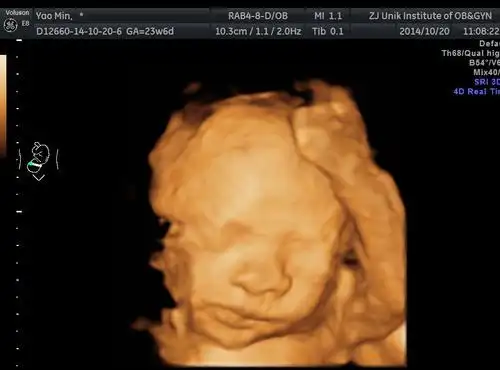

做完四维心态崩了…为啥我的宝宝这么丑

四维彩超和宝宝的长相差别大吗?这些特征存在误差,丑俊难辨

胎宝四维照片丑哭那生出来会不会丑看完之后孕妈就能放心了

被宝宝的四维彩超照丑哭了?不是医生技术不好,而是有客观原因的

四维彩超回来,感觉宝宝好丑啊!

孕妇做四维彩超胎儿鼻子扁又大胎儿也是有苦说不出啊